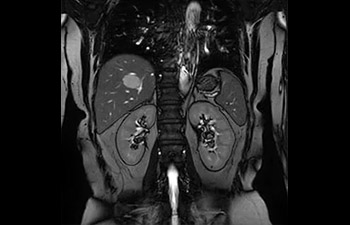

En una sociedad en la que los reembolsos son cada vez menos cuantiosos y las enfermedades crónicas se traducen en un aumento de los procedimientos de RM y en tiempos de espera más largos, los servicios de radiología se ven sometidos a una presión cada vez mayor. La aceleración pone en riesgo la calidad de la imagen o bien se puede aplicar a todo el espectro de las exploraciones rutinarias. Por lo tanto, para satisfacer la creciente demanda de productividad, todavía es necesario dar un paso adelante más en cuanto a la aceleración. Aprovechando nuestra dilatada posición de liderazgo en el ámbito de la velocidad (de la mano de SENSE), Philips presenta Compressed SENSE, un avance en términos de productividad.

• Es una innovadora técnica de aceleración que no solo permite agilizar las secuencias, sino todo el estudio. • Implementación especial con la que las exploraciones en 2D y 3D pueden llegar a ser hasta un 50% más rápidas con una calidad de imagen prácticamente equivalente.1

• Se puede usar con todos los contrastes y con todas las regiones anatomías.